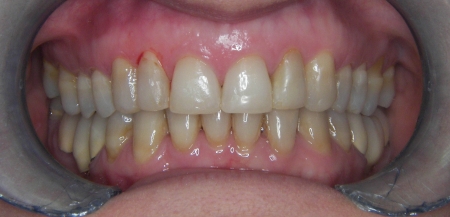

Slučaj 1: ispravljanje otvorenog zagriza i kompresije Invisalign full terapijom

Slučaj 2: ispravljanje kompresije Invisalign full terapijom- u ovom slučaju je izvađen jedan donji sjekutić

Slučaj 3: ispravljanje kompresije Invisalign full terapijom

Slučaj 4: ispravljanje kompresije Invisalign full terapijom

Slučaj 5: ispravljanje kompresije i križnog zagriza Invisalign full terapijom

Slučaj 6: ispravljanje kompresije i dubokog zagriza Invisalign full terapijom

Slučaj 7: ortodontska predprotetska terapija Invisalign full